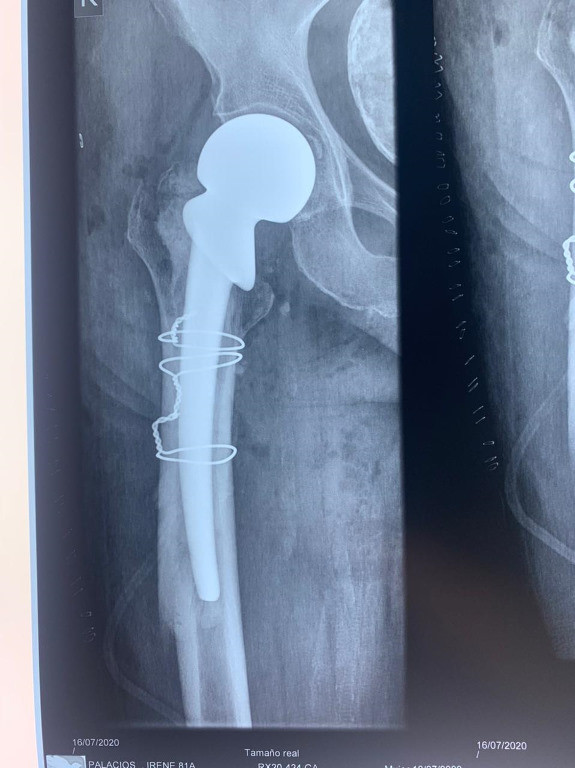

Caso de Fractura de Fémur

Envíado por Dr. Ronald Napoleón Ruano Mendoza